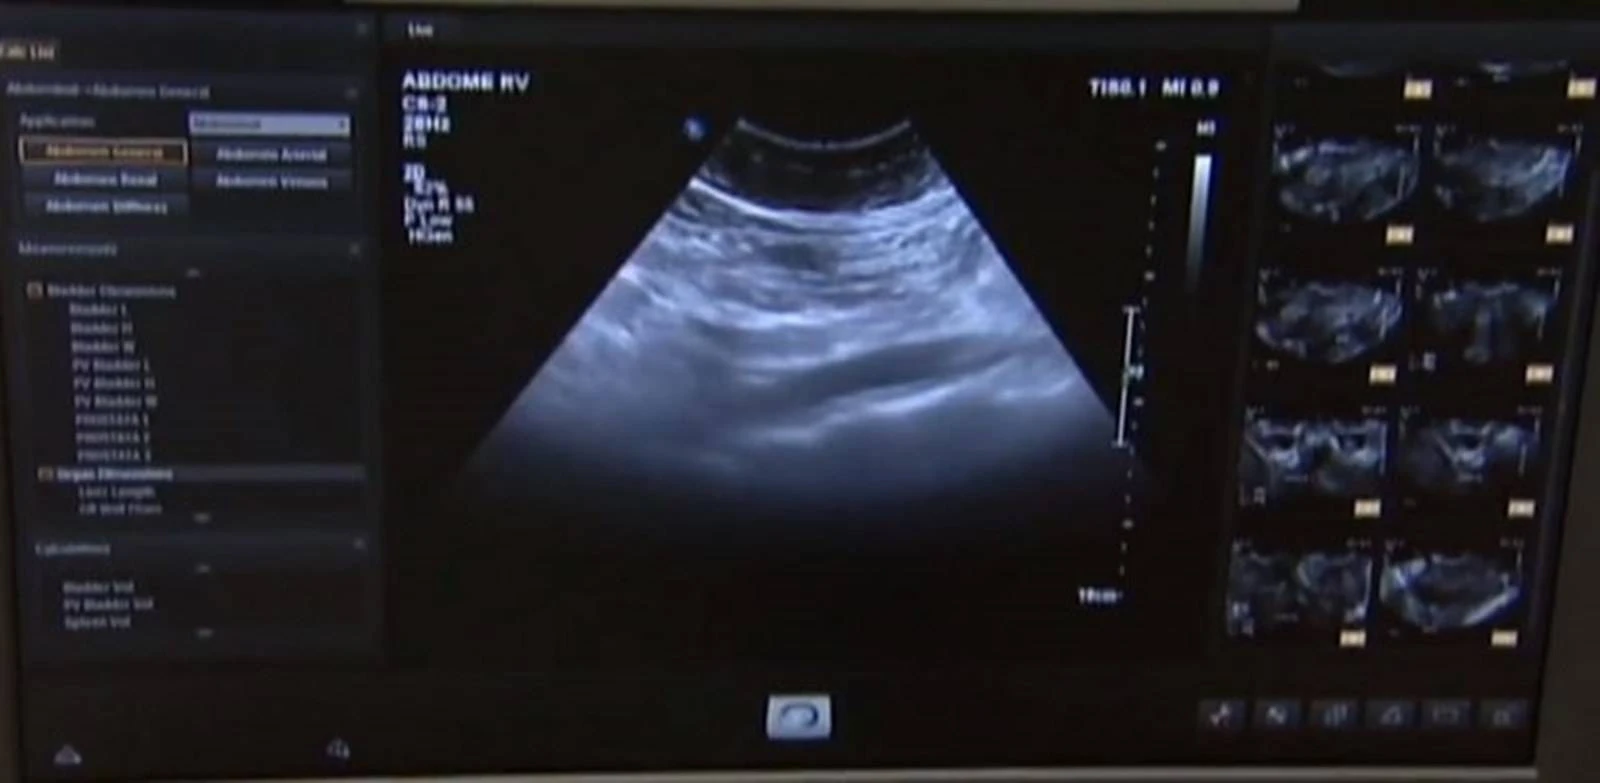

Comissão debate uso de ultrassonografia pulmonar no diagnóstico de Covid-19

A Comissão Externa que acompanha as ações de combate ao coronavírus debate hoje as indicações e a possibilidade de uso da ultrassonografia pulmonar no diagnóstico e acompanhamento de pacientes com Covid-19.